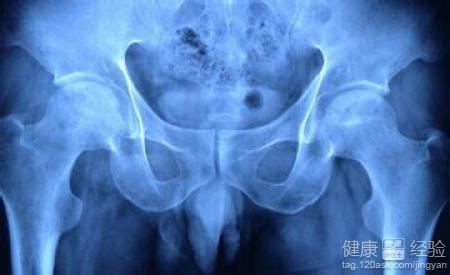

股骨头坏死是一种常见的骨关节疾病,可发生于任何年龄,但以31-60岁最多。主要表现为髋关节持续性疼痛,再由疼痛引发关节活动受到限制,最后导致残疾,生活无法自理,一个病人拖累一个家庭。现代医学目前尚无有效的治疗药物。

毛X,男,39岁,饭店老板,双髋关节疼痛多年,需拄双拐走路,经多家医院CT检查,确诊为股骨头缺血坏死,多方求医未见好转,后慕名到我处就诊,给予本方治疗,二十余天疼痛大减,可以不用拄拐独自行走,连续服药半年后复查CT,报告提示塌陷的股骨头已经长平,检查医生都感到很惊奇。后来又服药三个月巩固疗效,至今未见复发。